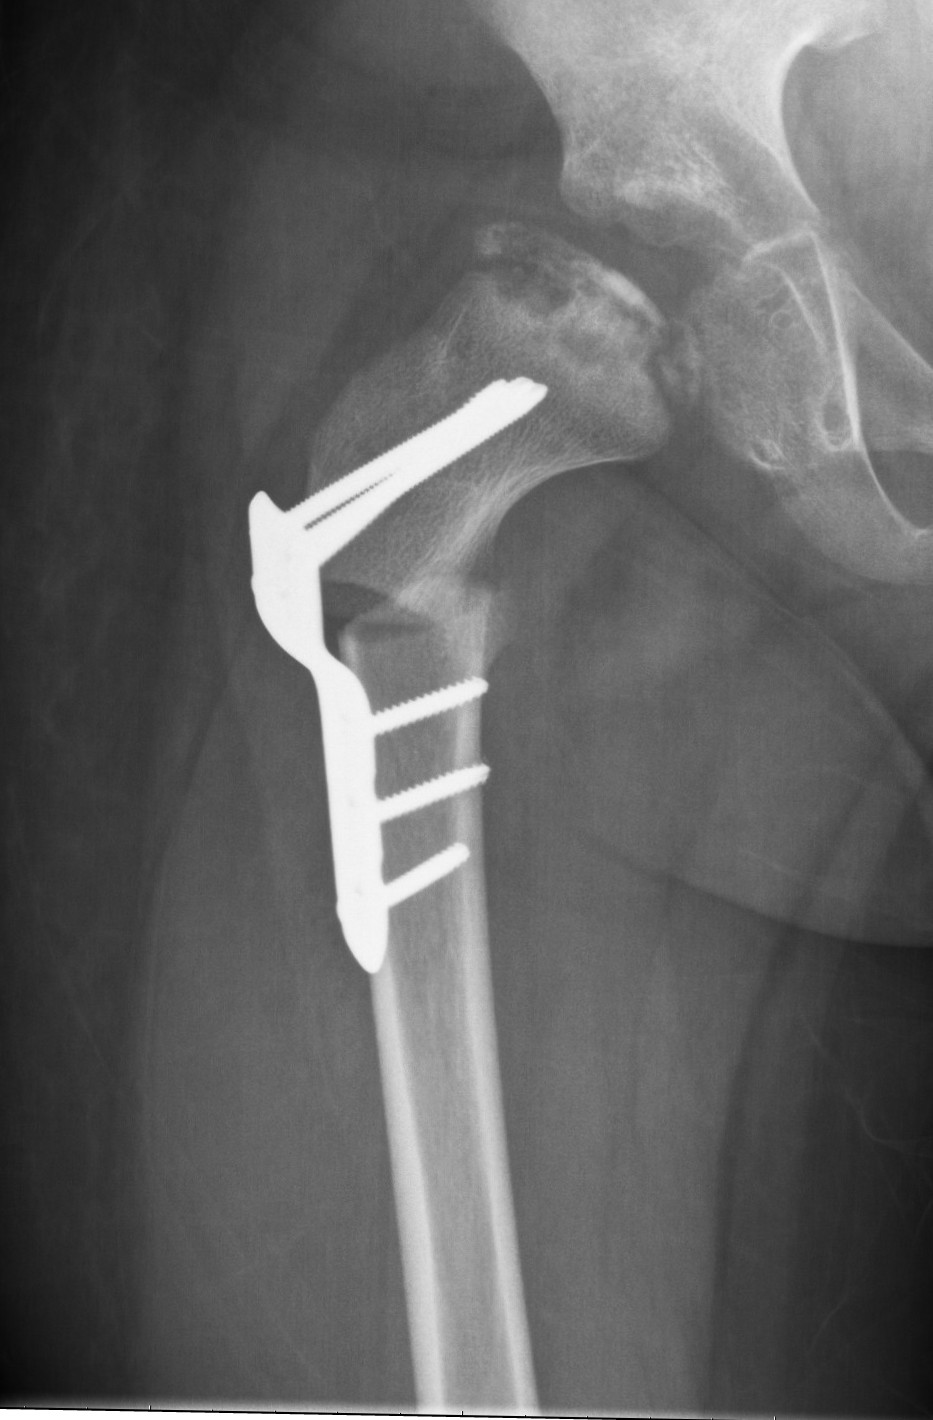

Legg-Calvé-Perthesin tauti johtuu reisiluun pään verenkiertohäiriöstä, jonka syy on tuntematon. Verenkiertohäiriön seurauksena reisiluun pään luutumistumake menee osittain kuolioon, jonka vuoksi reisiluun pään muoto muuttuu ja lonkkaan kehittyy liikerajoitusta ja kipua. Tautia esiintyy leikki- ja kouluikäisillä lapsilla, pojilla enemmän kuin tytöillä. Paranemisprosessi voi kestää useita vuosia. Taudin ennuste on yleensä hyvä, mikäli se alkaa ennen esikouluikää. Vaikeimmillaan tauti voi johtaa lonkan liikerajoitukseen, alaraajojen pituuseroon ja ennenaikaiseen nivelrikkoon aikuisiällä.